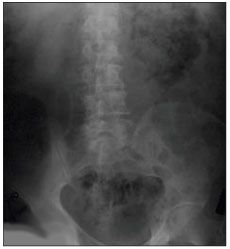

Figure 1 – Gas surrounding the left kidney is seen in this radiograph of the abdominal area.

An abdominal radiograph revealed gas surrounding the left kidney (Figure 1), and a CT scan of the abdomen and pelvis showed a large area of gas and fluid in the left renal fossa within the Gerota fascia (Figure 2). Percutaneous drainage of the abscess was performed using a 10 French Cope loop all-purpose drainage catheter. A diagnosis of EPN was made.